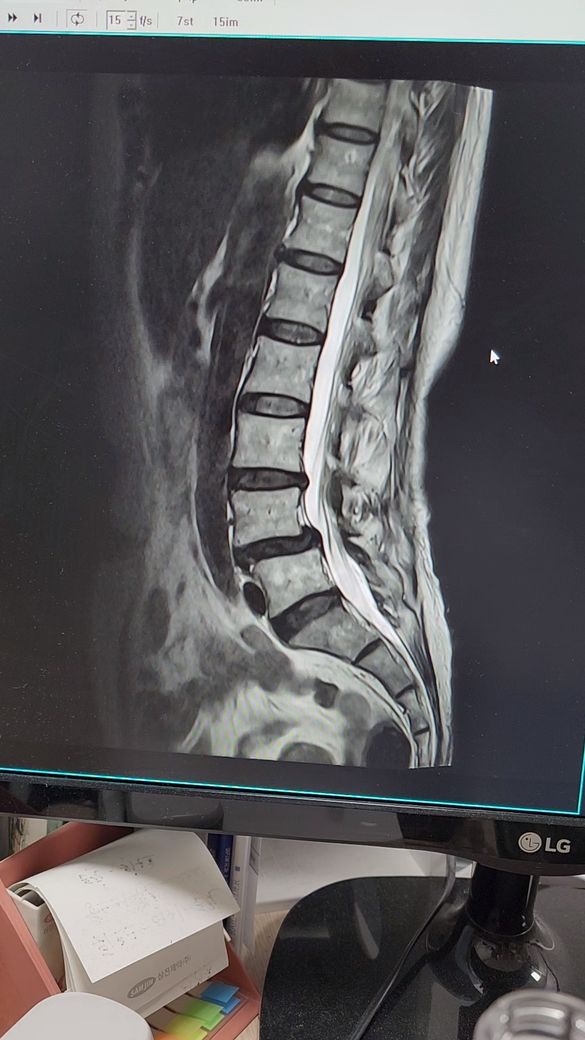

허리디스크 추간판탈출증.전방전위증

4월5일 척추,4.5번

추간판탈출증과 전방전위증으로 왼쪽 엉치부분과 사타구니 허벅지 뒷쪽 방사통과 다리저림이 심해요.처음엔 걷지도 못하고 한달반정도 물리치료,도수치료.약물치료하다가 좋아지질않아서

스테로이드주사4번 맞고 약처방받아서 먹고있는데 통증이 줄었다 심했다 해요. ㅈㅅㄱ교수님동영상보며 걷기도 한시간씩 참아가며 보존치료로 버티고있는데 나날이 통증변덕이심해요. 파행거리가 10분정도.때로는 20분도 괜찮아 지기도하는데 일관성이없어요. 한방 약침치료도 한달해 봤는데 통증이 호전되지않아요. 이럴때 도수치료나 교정치료가 도움이 될까요?